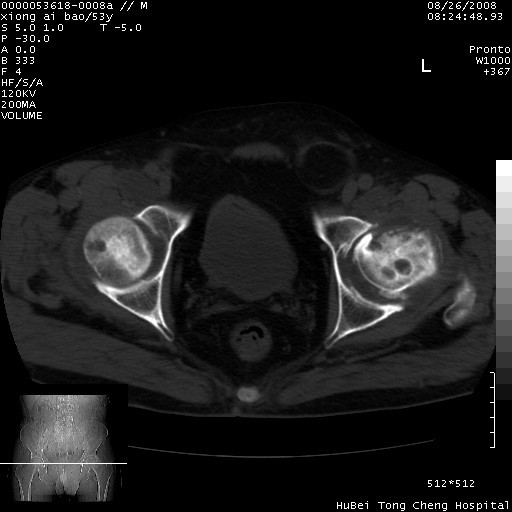

标题: CT15583:M,53Y。请老师指教分析骨盆及其他病变。 [打印本页]

标题: CT15583:M,53Y。请老师指教分析骨盆及其他病变。

股骨头坏死/腹股沟疝。

双侧股骨头无菌坏死,左侧腹股沟斜疝。

非常典型病例,双侧股骨头坏死伴双髋关节周围软组织肿胀,左腹股沟疝。

双侧股骨头坏死伴双髋关节周围软组织肿胀,左腹股沟疝。

双侧骨股头无菌性坏死,左侧腹股沟疝

双侧髋关节肿胀明显,感觉还不能排除结核。

考虑双侧髋关节结核,左侧腹股沟疝